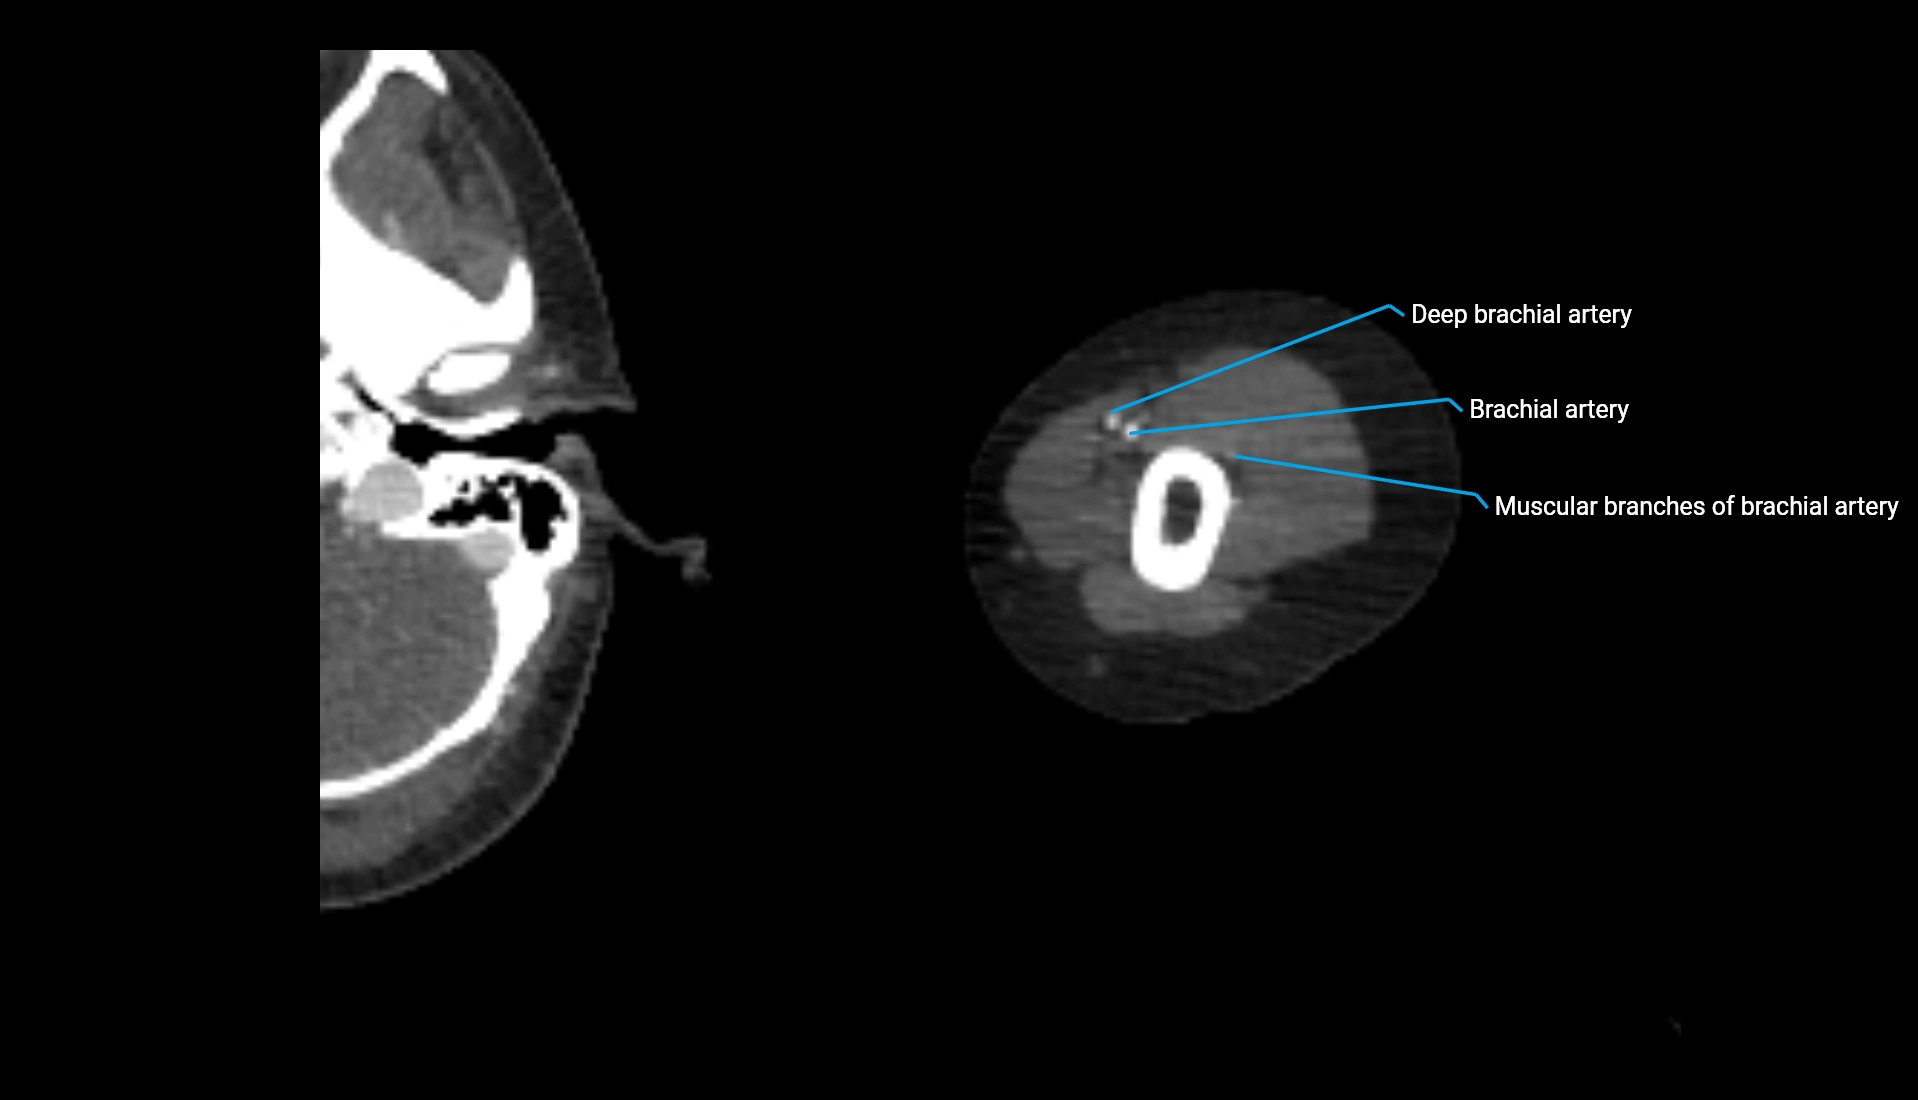

CT Appearance

Non-Contrast CT:

• Cortex: High-density, sharply defined

• Subchondral bone: Dense cancellous matrix

• Articular surface: Smooth concave contour articulating with the capitellum

• Excellent for evaluating bone integrity, alignment, and subtle fractures

Post-Contrast CT:

• Bone: No enhancement

• Joint capsule and synovium: Mild enhancement outlining the joint

• Improves contrast between soft tissues and bony margins

• Useful in detecting subtle joint abnormalities or postoperative changes